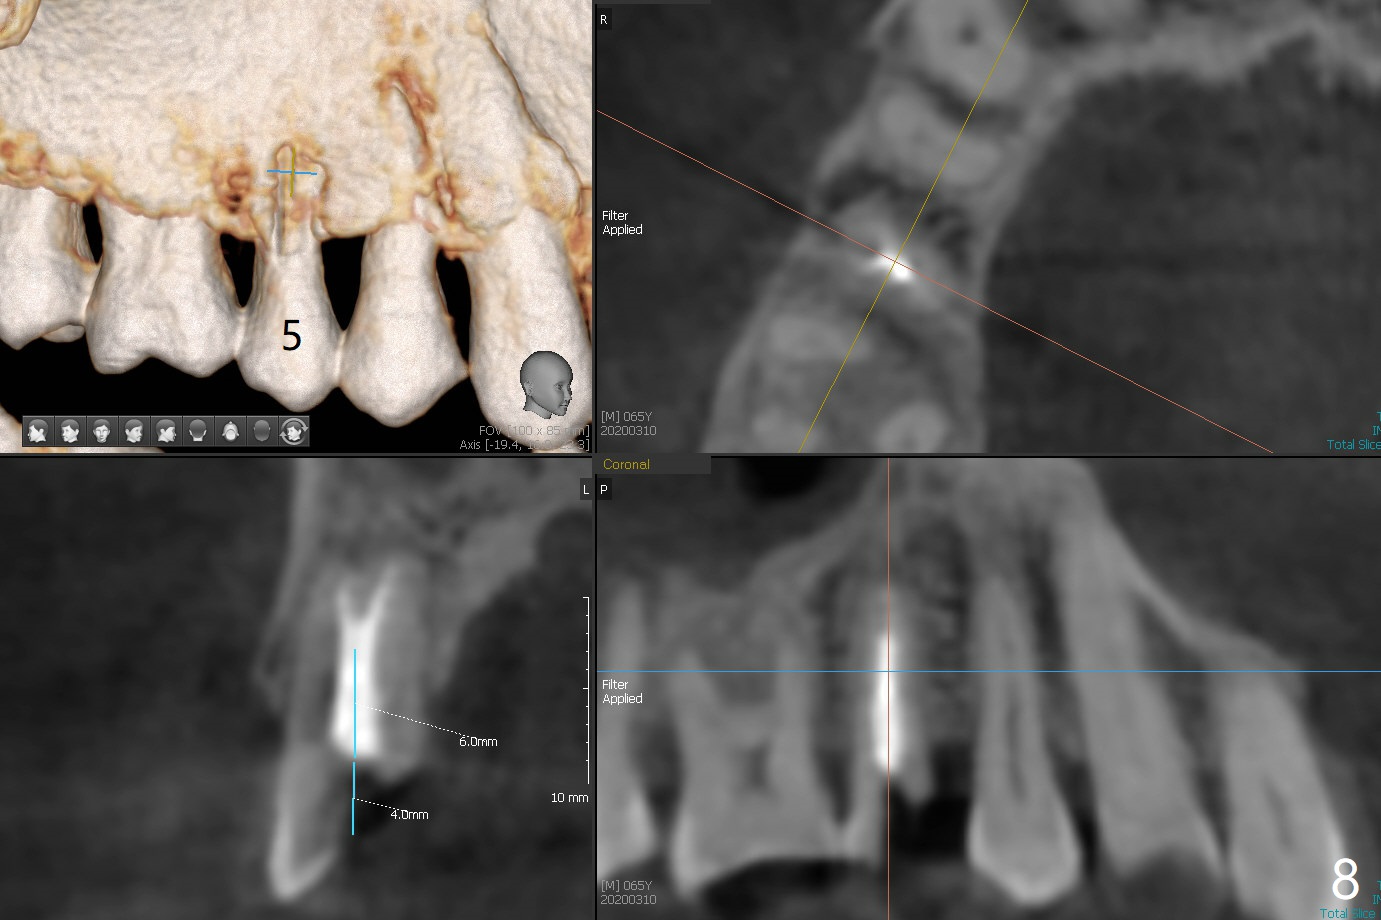

A 65-year-old man cracks 3 teeth in ~2 years (Fig.1,2 (#4,13,15)). The tooth #4 is symptomatic after RCT (Fig.1); it appears that the buccal canal is incompletely filled (data not shown). In fact an exam 1 month later shows that the symptomatic tooth is #2 (crack), while #4 is salvageable (Fig.8). The tooth #13 has palatal subgingival fracture with severe pain (Fig.2 with palatal defect). In fact the title of this case is incorrect). After extraction, allograft is placed (Fig.3 *) with 6-month membrane. In fact the bone graft is not packed into the apex of the socket; a condenser should have been used. The patient returns 3 days postop before leaving abroad. The 6-month membrane remains in place (Fig.4), while the ridge at #15 is minimally atrophic (Fig.5). The coronal lamina dura becomes indistinct 5 months postop (Fig.6). The bone graft remains in the socket. The distoapical portion of a 4x11.5 mm implant may be in the sinus (Fig.7).